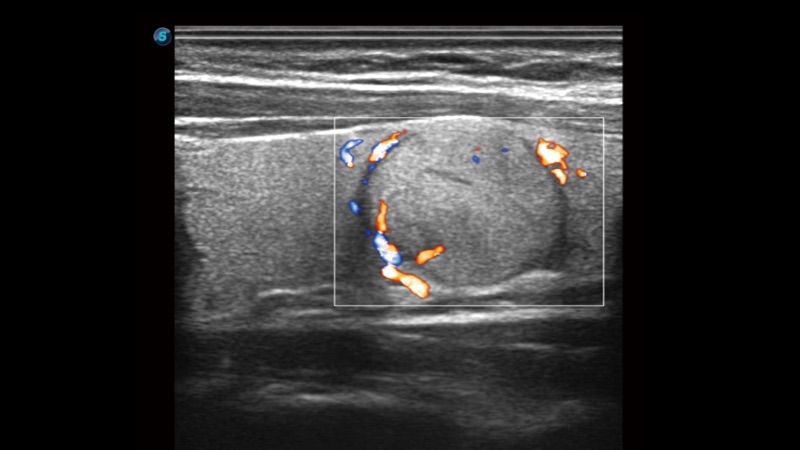

弹性成像

弹性成像无需高频度外力作用可真实反映组织的形变,具有良好的重复性,更早地洞察潜在的病理学特征。

临床图像